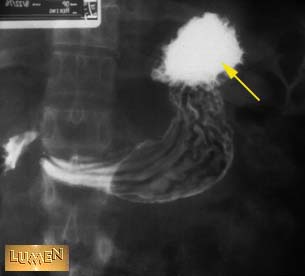

Question: Identify.

Answer

Fundus of stomach.